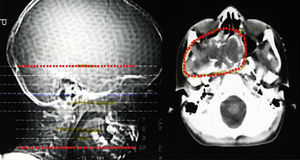

Descrição do casoDoente do sexo masculino, caucasiano, sem antecedentes pessoais ou familiares relevantes, com diagnóstico de rabdomiossarcoma do seio maxilar direito aos 5 anos de idade. Como tratamento realizou uma perfusão de quimioterapia intratecal com metotrexato e prednisolona e quimioterapia intravenosa com vincristina, actinomicina e ifosfamida (doses totais não disponíveis no processo). Foi submetido também a radioterapia (RT) cervical e submaxilar na dose total de 51Gy – a figura 1 mostra a TAC de planeamento da RT onde se pode verificar que a sela turca foi envolvida no campo irradiado. Aos 12 anos o doente foi referenciado à consulta de endocrinologia de reabilitação. Auxologicamente apresentava estatura de 139cm (percentil 10); estatura alvo familiar de 170cm (percentil 10); idade óssea de 9 anos; estádios de Tanner – pelos púbicos 2, genital 2, pelos axilares 2 – e volume testicular de 5mL. Realizou avaliação analítica – TSH (thyroid stimulating hormone) 7,4mUL/mL (0,3‐4,2); T4 livre 0,8ng/dL (0,9‐1,7); IGF‐1 (insulin‐like growth factor 1) 102ng/mL (<percentil 3); eixos gonádico e cortico‐suprarrenal sem alterações – e, posteriormente, prova de hipoglicemia insulínica, cujo valor máximo atingido de somatotropina foi 6,6ng/mL (normal>7) com correspondente glicemia de 45mg/dL. Portanto, apresentava hipotiroidismo primário, tendo sido medicado com levotiroxina 50μg/dia, e também deficiência parcial de somatotropina. No entanto, face aos critérios vigentes na altura em Portugal – uma vez que auxologicamente se apresentava dentro dos valores de normalidade e tinha sofrido uma doença oncológica – não apresentava indicação para terapêutica com somatotropina. Apesar de ter crescido no percentil 10 até por volta dos 14 anos, começou nesta altura a cruzar percentis, tendo a sua estatura final – 163cm – ficado aquém da estatura alvo familiar (fig. 2A). Progrediu autonomamente na puberdade, atingindo aos 17 anos (idade cronológica correspondente à óssea) estádio de Tanner 5 e volume testicular de 25mL. Contudo, o doente não realizou o surto pubertário (fig. 2B). Os níveis séricos de IGF‐1 permaneceram sempre abaixo do percentil 50, encontrando‐se, por vezes, inferiores ao percentil 3 (fig. 3A). Realizou ecografias tiroideias ao longo do seguimento que não revelaram alterações.